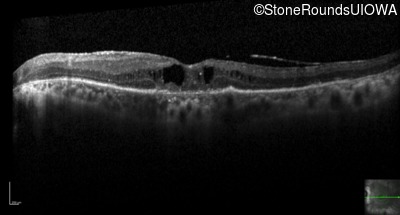

Optical Coherence Tomography - Right - 20/50 -1

Exemplar / OCT Stack

Optical Coherence Tomography - Left - 20/125